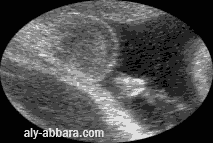

Organes génitaux externes masculins chez un fœtus de 36 SA

Cette image met en évidence l'aspect échographique du jet urinaire lors de la miction

Foetus du sexe masculin à 36 SA, en miction urinaire